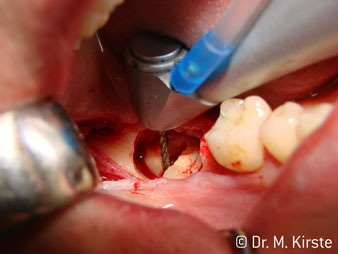

Le contre-angle avec tête angulée à 45° a surtout été choisi pour ses nombreux avantages. Les collègues qui exercent en chirurgie, et à qui cet instrument est principalement destiné, apprécieront très vite la possibilité de travailler efficacement dans des zones très étroites. En particulier, lors d’extractions de dent de sagesse (Ill. 2), où il n'y a pas besoin d’un grand angle d’écartement des tissus mous dans la région de la joue (Ill. 3). Pendant la préparation, une légère rotation de la tête de l’instrument permet un travail rapide et sans risque dans la zone rétromolaire.

En terme de rapidité, l'instrument peut atteindre jusqu’à 100 000 tr/min. Tandis qu'un spray très professionnel et une tête aux dimensions réduites répondent à toutes les exigences en matière de refroidissement et de visibilité de la zone de traitement.

La conception particulière des roulements à l'intérieur de la tête du contre-angle garantit un fonctionnement silencieux de l’instrument rotatif et lui procure une grande efficacité de coupe, sans à-coup ; ce qui est appréciable lors des interventions chirurgicales comme par exemple les séparations dentaires et résections apicales (Ill. 4-9).